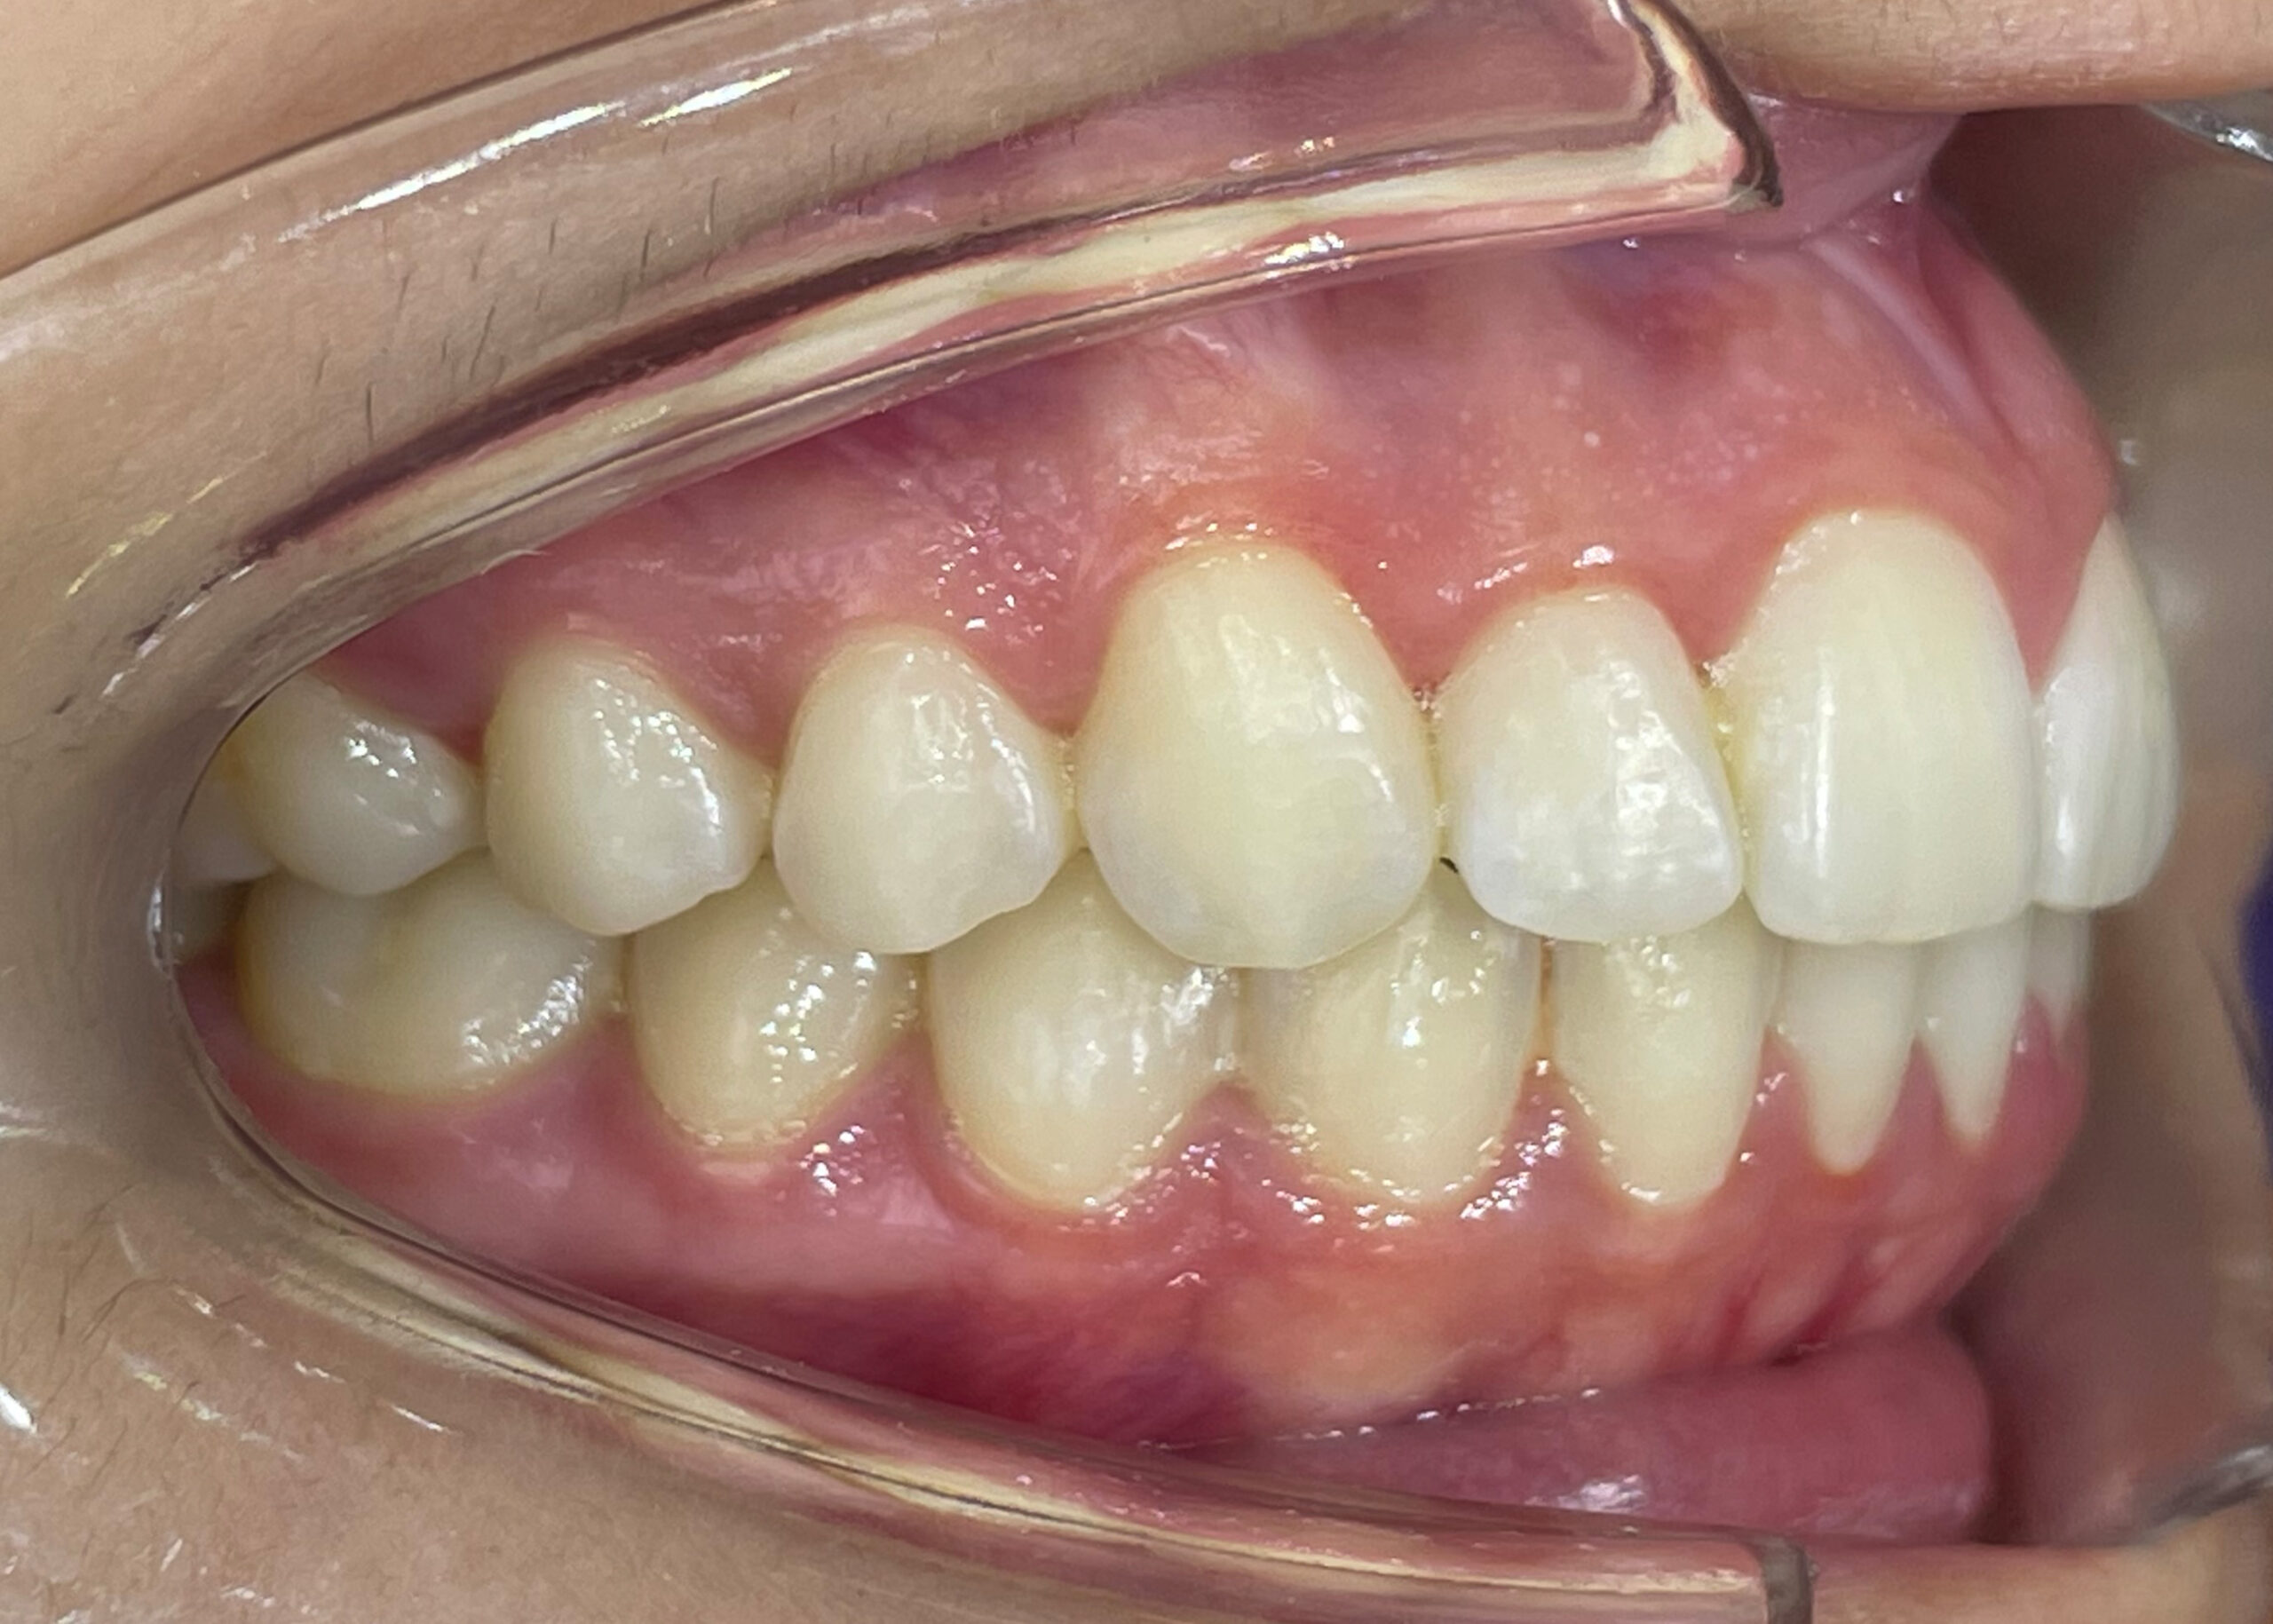

Al termine del trattamento, vale a dire solo 8 mesi dopo, l‘analisi cefalometrica di controllo ha indicato un miglioramento degli assi incisivi nonostante la correzione di una DDM moderata.

Gli allineatori SPARK hanno pertanto consentito al Dr. Pierre-Antoine Dian di ottenere una buona espansione delle arcate, un perfetto controllo del torque e una risoluzione dell‘affollamento anteriore grazie ai protocolli utilizzati e alla predicibilità dei movimenti oltre alla flessibilità fornita dal software Approver.